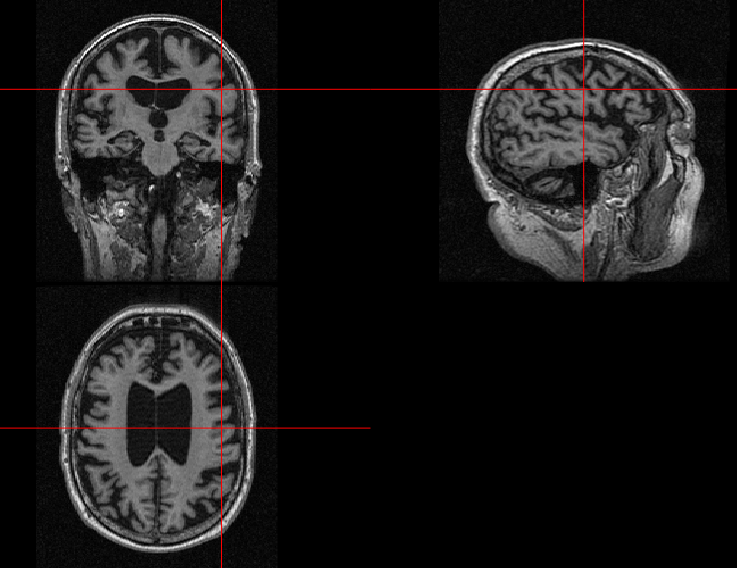

2.2.3 Skull Stripping

This pre-processing technique removes the skull voxels from the T1-weighted MRI scan. To do this operation on the N4 bias-corrected image, FSL software [18] was used, which is integrated into R using the fslR package. Fslr performs required operations on NIfTI image objects using FSL commands and returns them as R objects [15]. The function fslr::fslbetfslr::fslbet is readily available, which takes in the N4 corrected NIfTI image and calls the FSL BET function to perform skull stripping. Brain Extraction Tool (BET) [19] uses a deformable model that evolves to fit into the brain tissue surface locally adaptive model forces. To form a brain tissue mask which can be overlayed into the input scan, an NIfTI array is created and filled with binary ones using dimensions information from the header file. Secondly, the areas of the skull-stripped image containing the brain tissue were determined, or every pixel with a positive intensity value, because the skull stripping algorithm BET sets everything that is not brain to binary zeroes. A centre of gravity (CoG) of the extracted tissue was determined during the first iteration, and the algorithm was repeated by feeding the CoG as additional information to improve the skull stripping paradigm as one single iteration was observed to contain deformities. Bias correction, explained in the previous subsection, is essential for this step as the skull stripping algorithm heavily depends on the tissue intensities and a low variation in the field can hinder the output. The skull-stripped image thus obtained is shown in Fig 4.

Refer to caption

(a)

(b)

Figure 4: Skull Stripping: (a) Brain tissue mask overlay (b) Extracted brain tissue